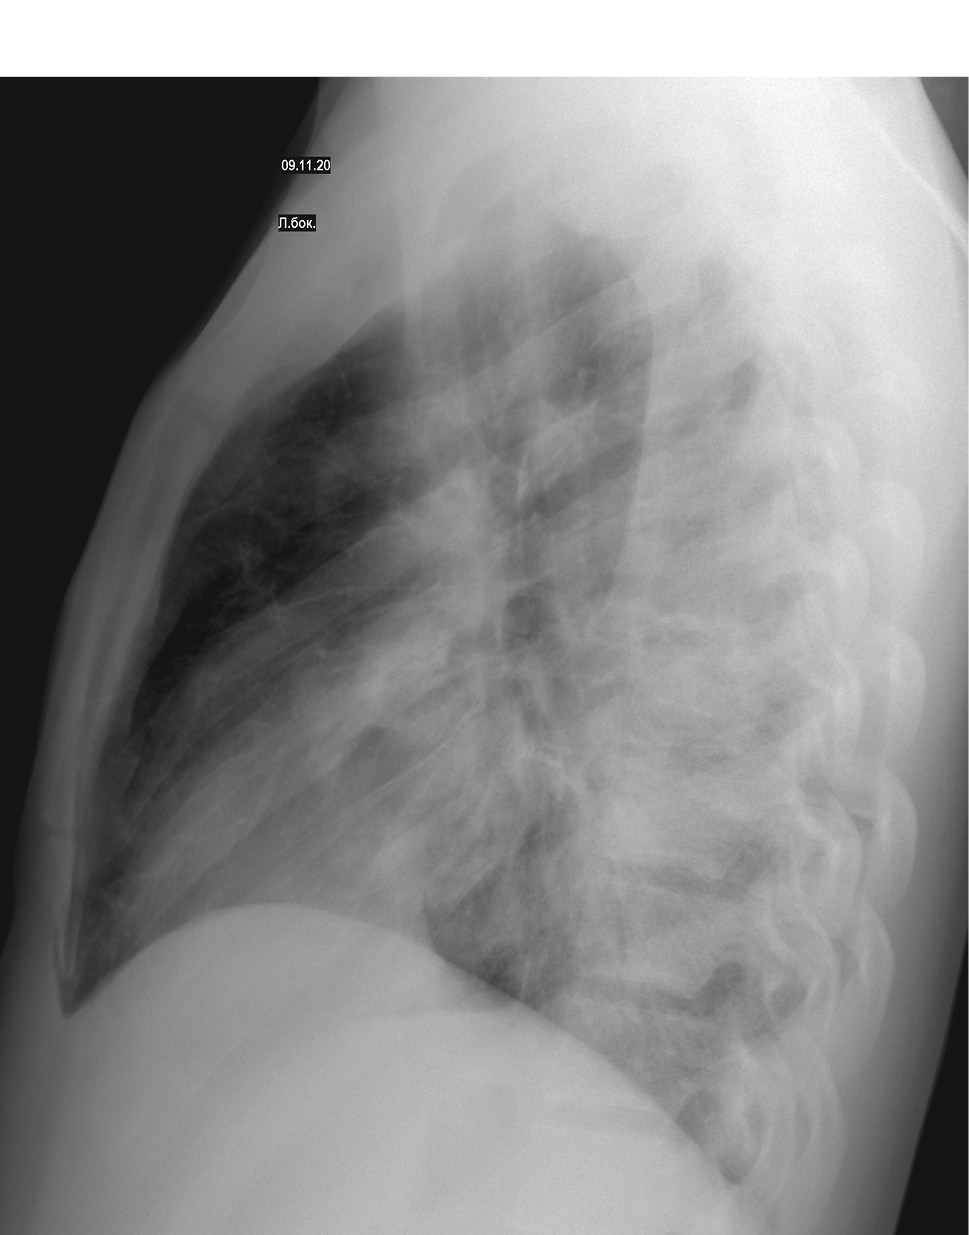

На фоне проводимой терапии у пациента в клинике сохранялись диарейный синдром, интоксикация, гипертермия. Состояние ребенка ухудшилось за счет появления признаков дыхательной недостаточности (затруднения дыхания, одышки, падения сатурации). В динамике выполнена контрольная рентгенография органов грудной клетки 09.11.2020: по сравнению с предыдущей обзорной рентгенограммой № 5189 от 06.11.2020 — отрицательная динамика в виде появления новых очагов слева и справа; двусторонняя очагово-сливная пневмония: справа — S4, S5 средней доли и S8, S9 нижней доли, слева — S4, S5 верхней доли S8, S9, S10 нижней доли (рис. 1, 2, 3).

Рисунок 1. Рентгенологическое исследование легких в прямой проекции

Рисунок 2. Рентгенологическое исследование легких в правой боковой проекции

Рисунок 3. Рентгенологическое исследование легких в левой боковой проекции

На рентгенограмме органов грудной клетки в динамике от 16.11.2020 отмечена положительная динамика с признаками уменьшения инфильтрации легочной ткани.